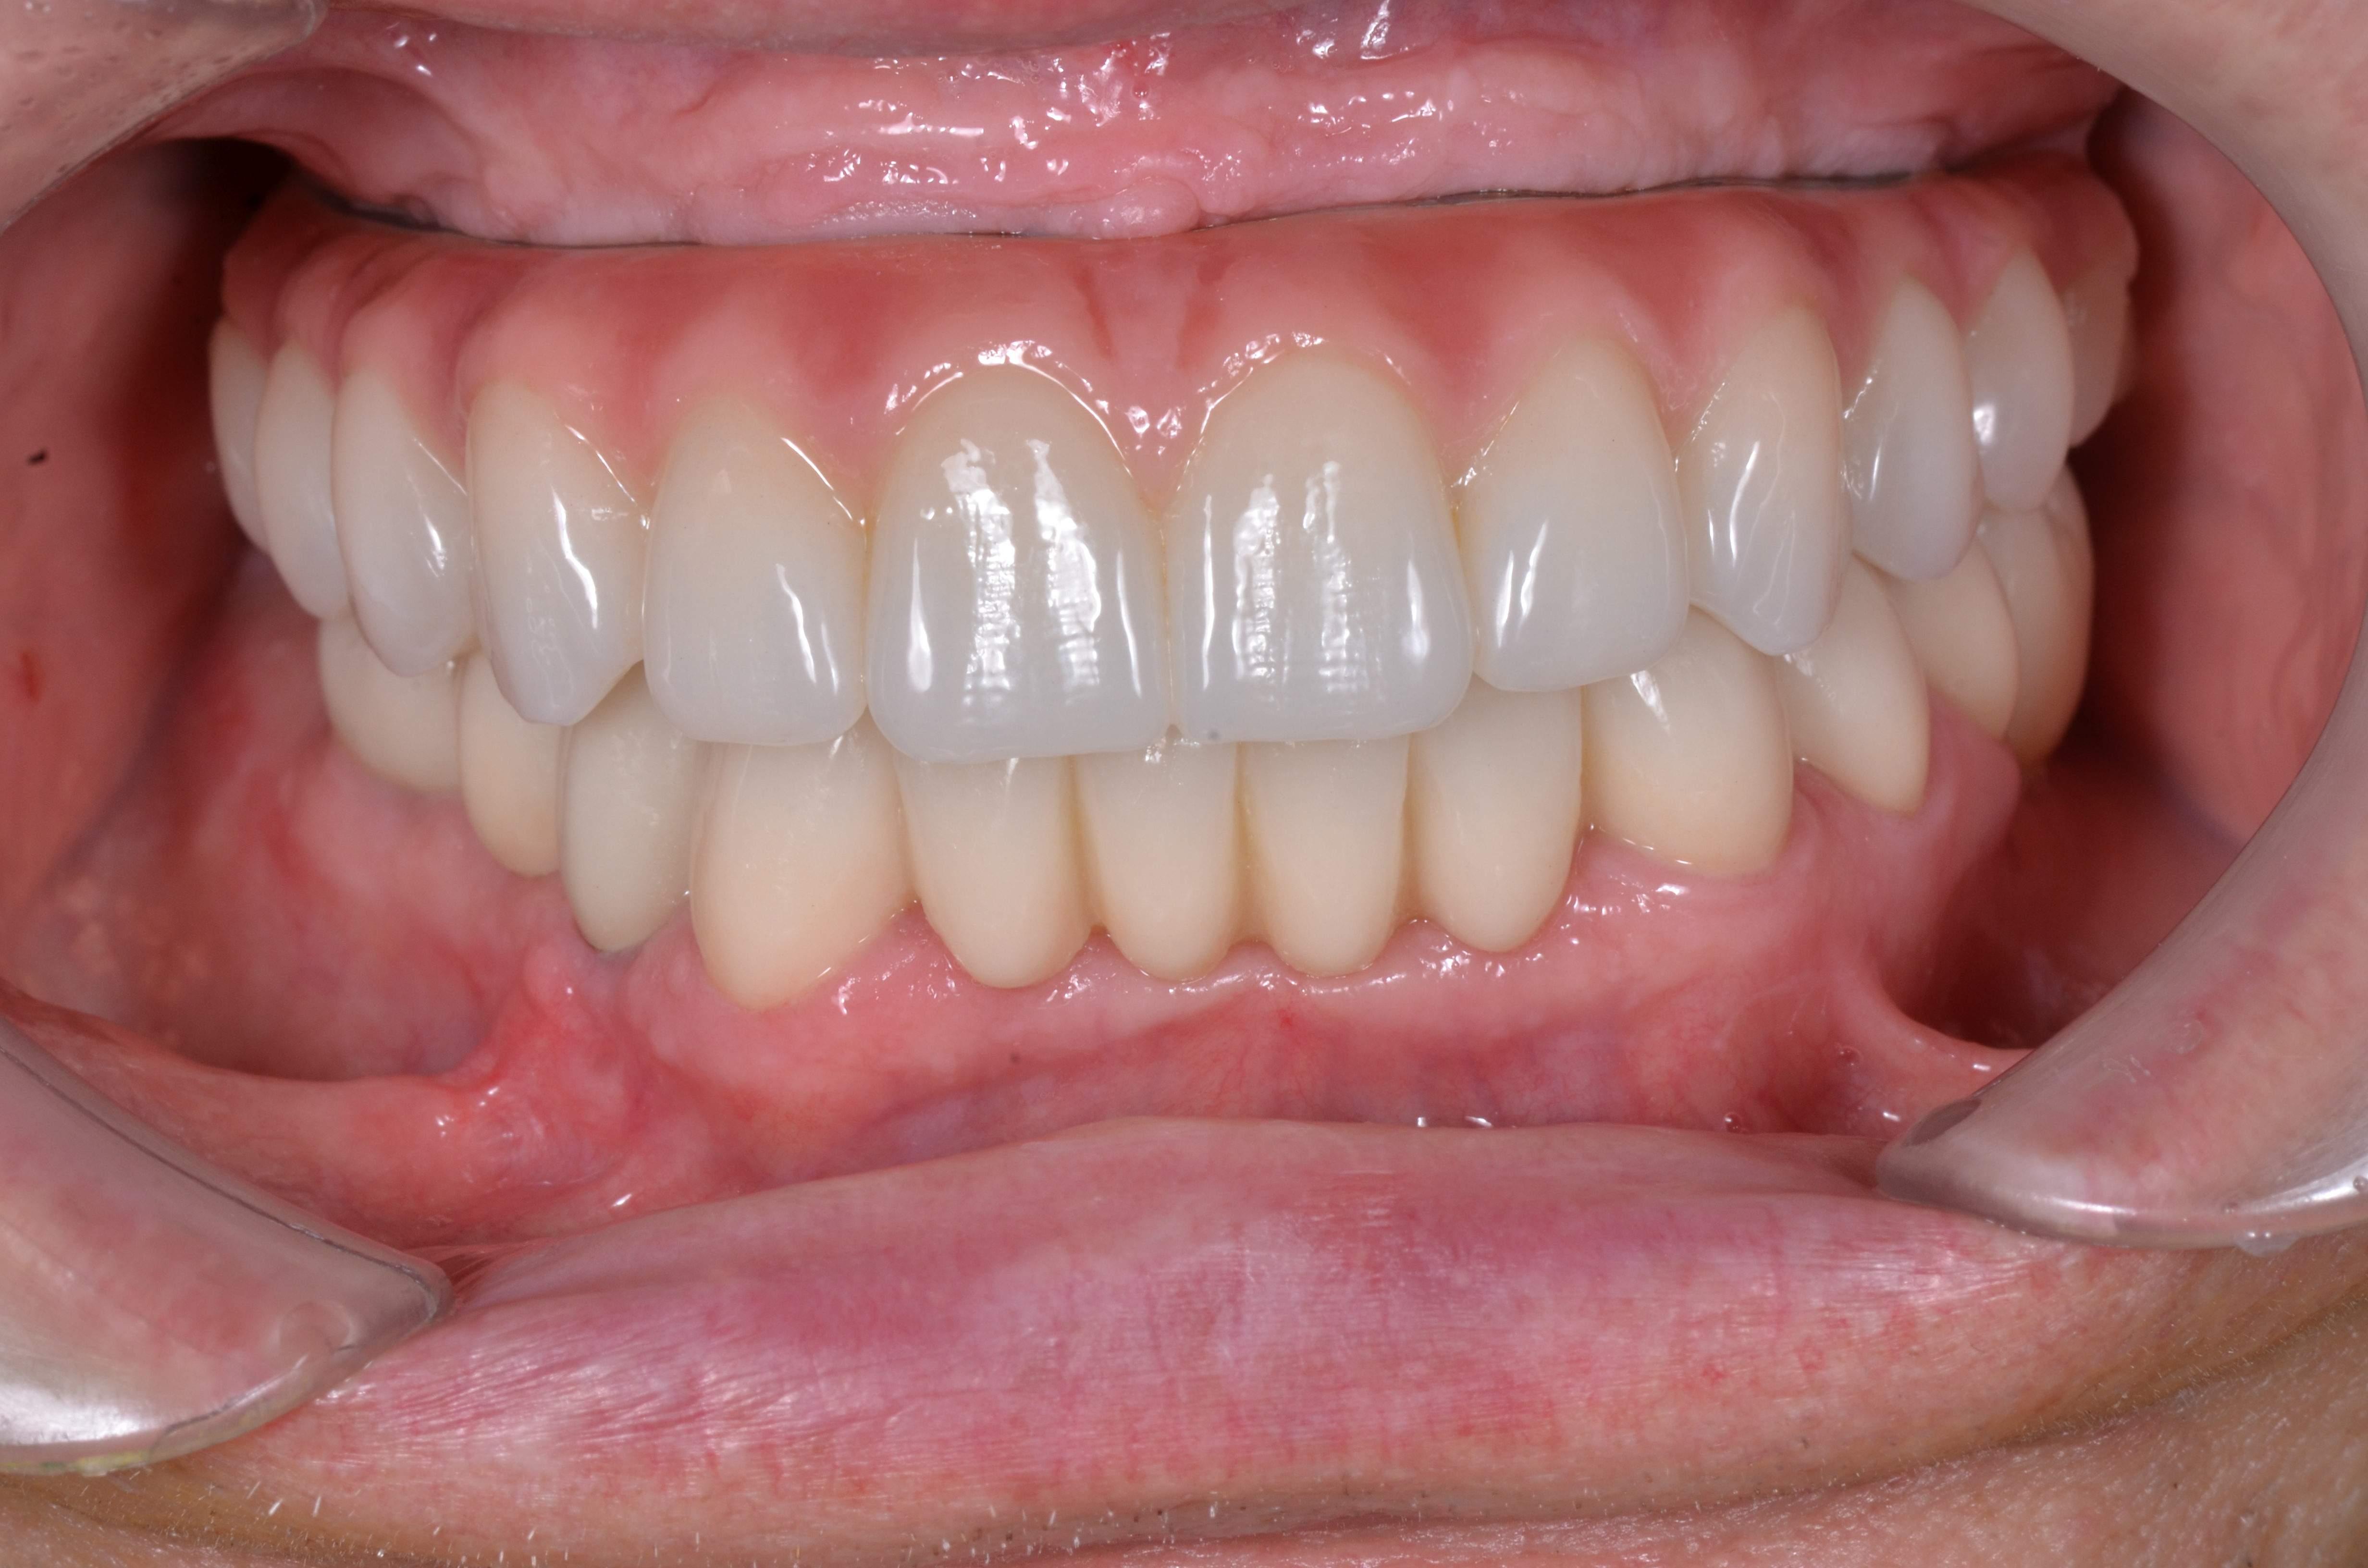

Благодаря междисциплинарному подходу при реабилитации стоматологических пациентов и богатому опыту нашей команды, нам удалось полноценно восстановить зубной ряд не только с эстетической точки зрения а, также восстановить его все функциональные параметры (рис. 47, 48,49).